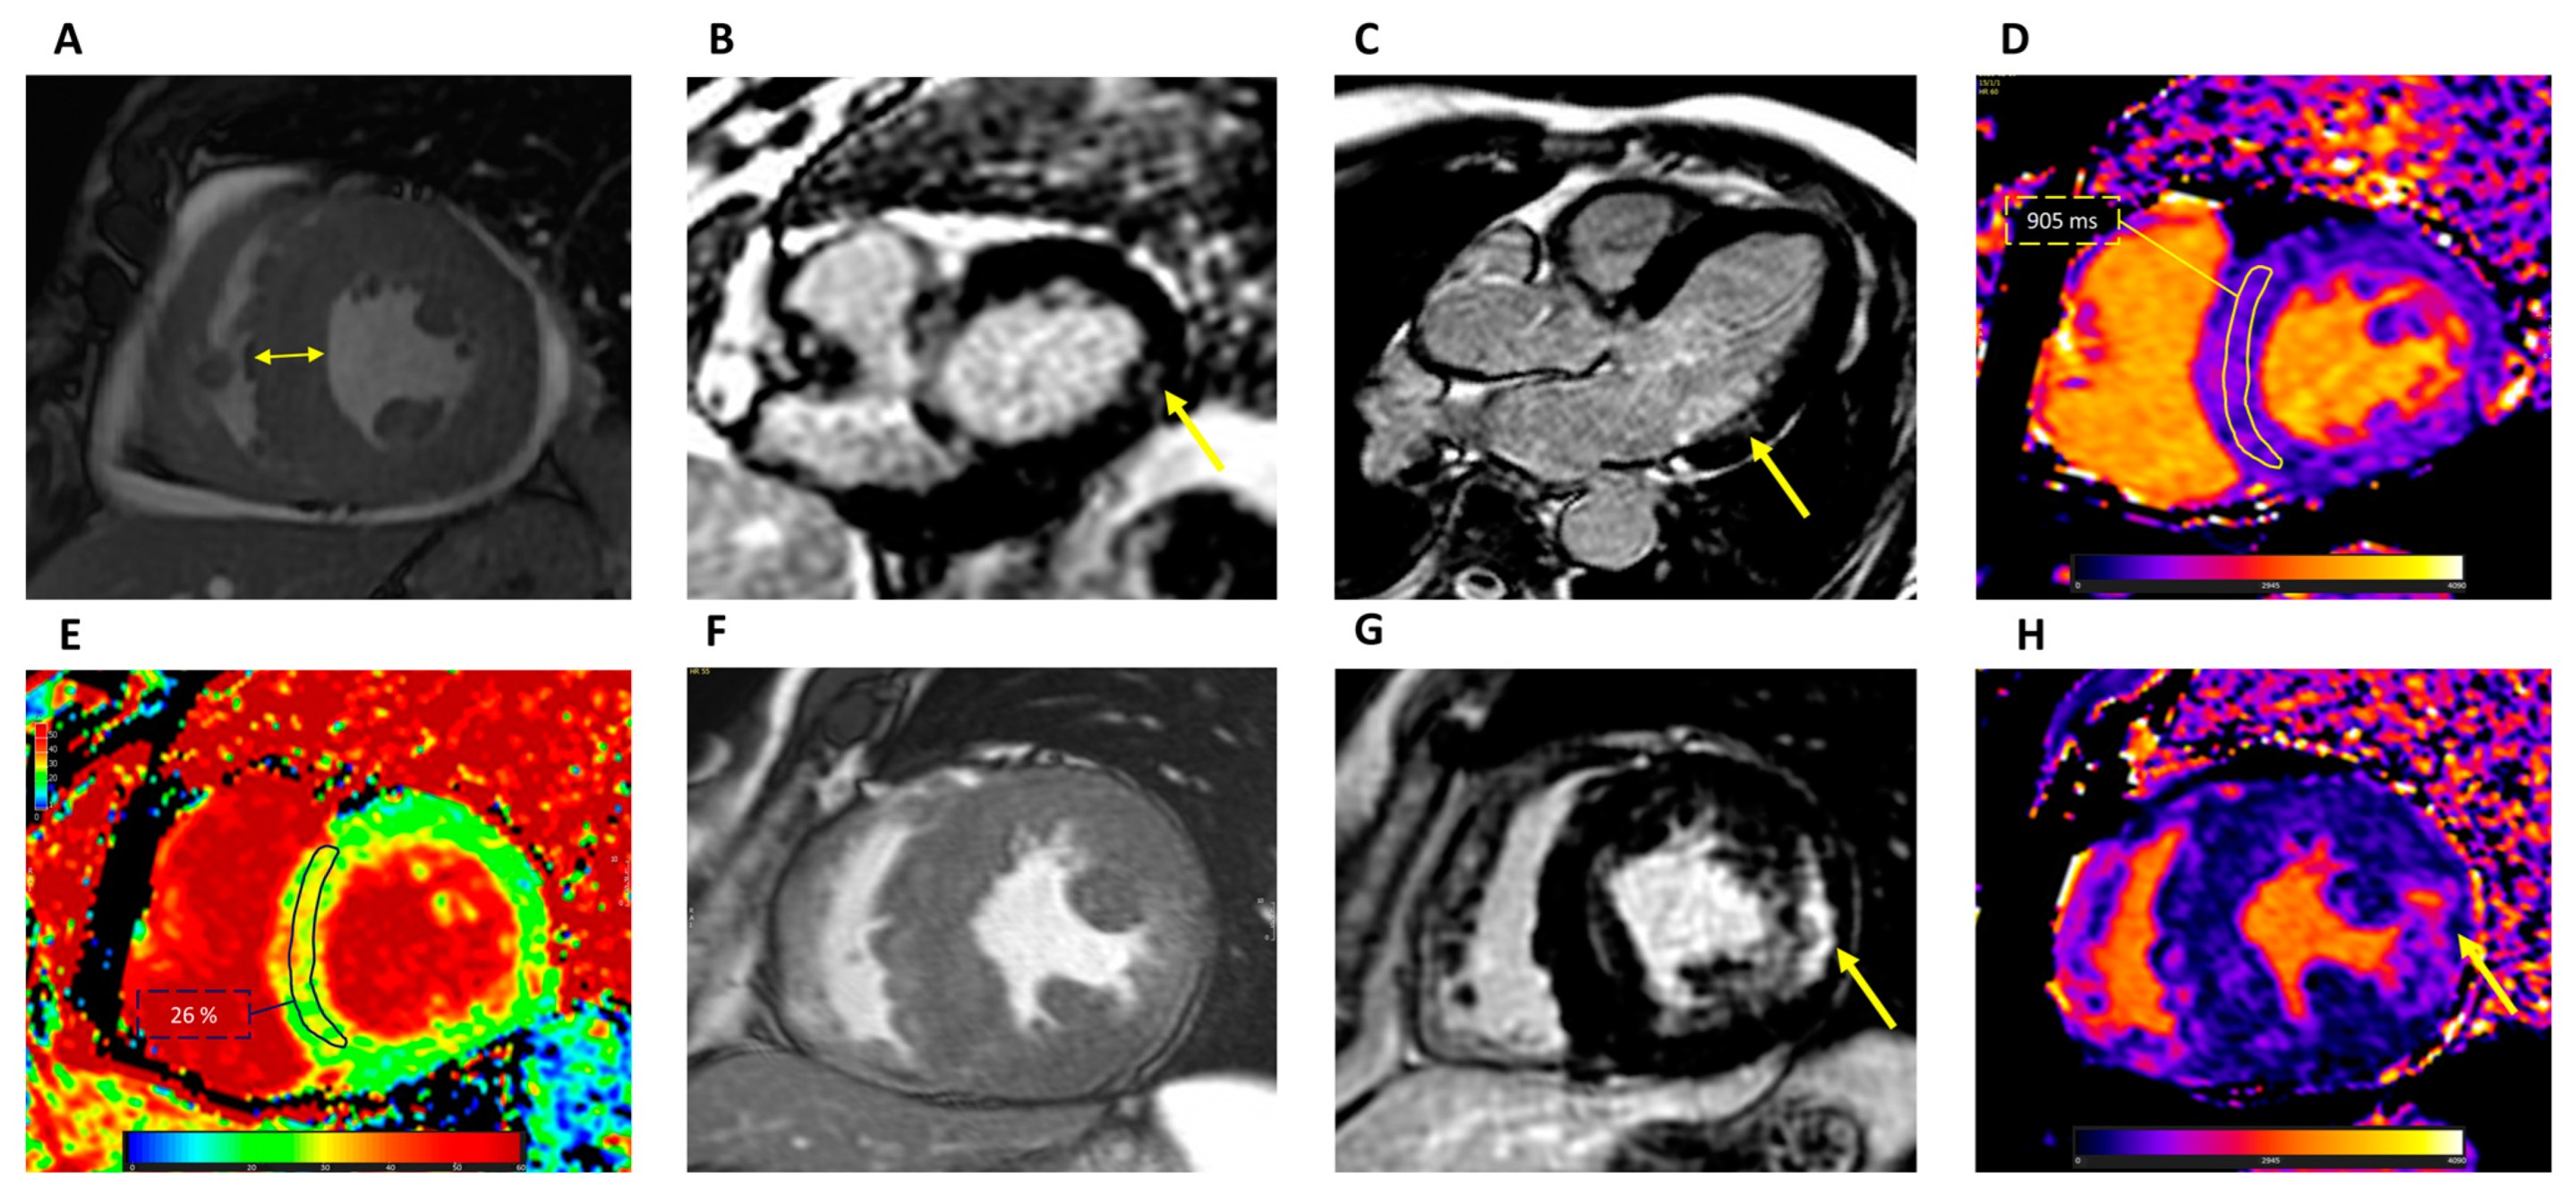

2.2. Cardiovascular Magnetic Resonance

3.1.2. Cardiovascular Magnetic Resonance

3.2.2. Cardiovascular Magnetic Resonance

| Reduced tissue Doppler strain [23] | Basal inferolateral LGE [35] |

| Reduced GLS [17,18] | Reduced global native T1 (may be normal or increased in advanced stages) [38,39] |

| Abnormal basal inferolateral regional strain [19] | Normal ECV (may be increased in advanced stages) [43] |

| Loss of basal-to-apex circumferential strain gradient [22] | Elevated T2 in the basal inferolateral wall [44] |

| Late gadolinium enhancement | Mid-wall or subepicardial basal inferolateral [35] | Mid-wall in most hypertrophied segments and RV insertion points [53,55] |

| T1 mapping | Global native T1 reduced; normal or elevated in advanced disease [38,39] | Normal or elevated T1 values [52,56] |

| Extracellular volume | Generally normal [43] | Generally normal or elevated [57] |

| T2 mapping | Elevated values in the basal inferolateral wall [44] | Sometimes elevated values in severely hypertrophied segments [57] |